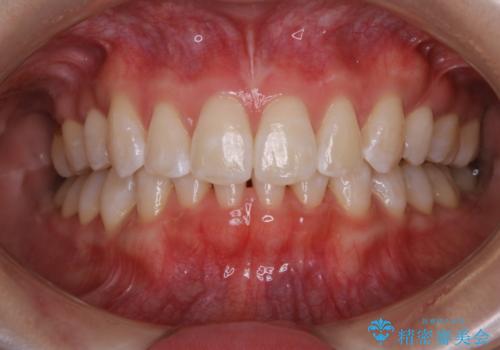

- オフィスホワイトニング希望で1日で白くしたいとのことでした。

オフィスホワイトニングのエクセレントコース(¥29700)を行いました。